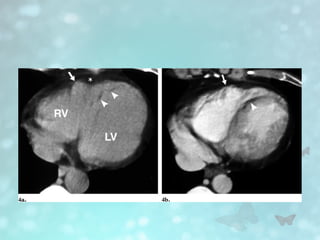

• #16  T1-weighted MR image shows fat infiltration of both ventricles. There is diffuse fat within right ventricular free wall (arrowhead) in addition to focal fat in left ventricular wall (arrow). Fatty infiltration of both ventricles is rare in arrhythmogenic right ventricular cardiomyopathy.